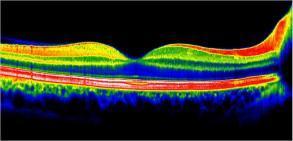

OCT MACULAIRE

Tomographie à cohérence optique s'intéressant à la macula

Examen réalisé dans la DMLA, le diabète, les membranes épirétiniennes, les trous maculaires et toutes les altérations de la macula